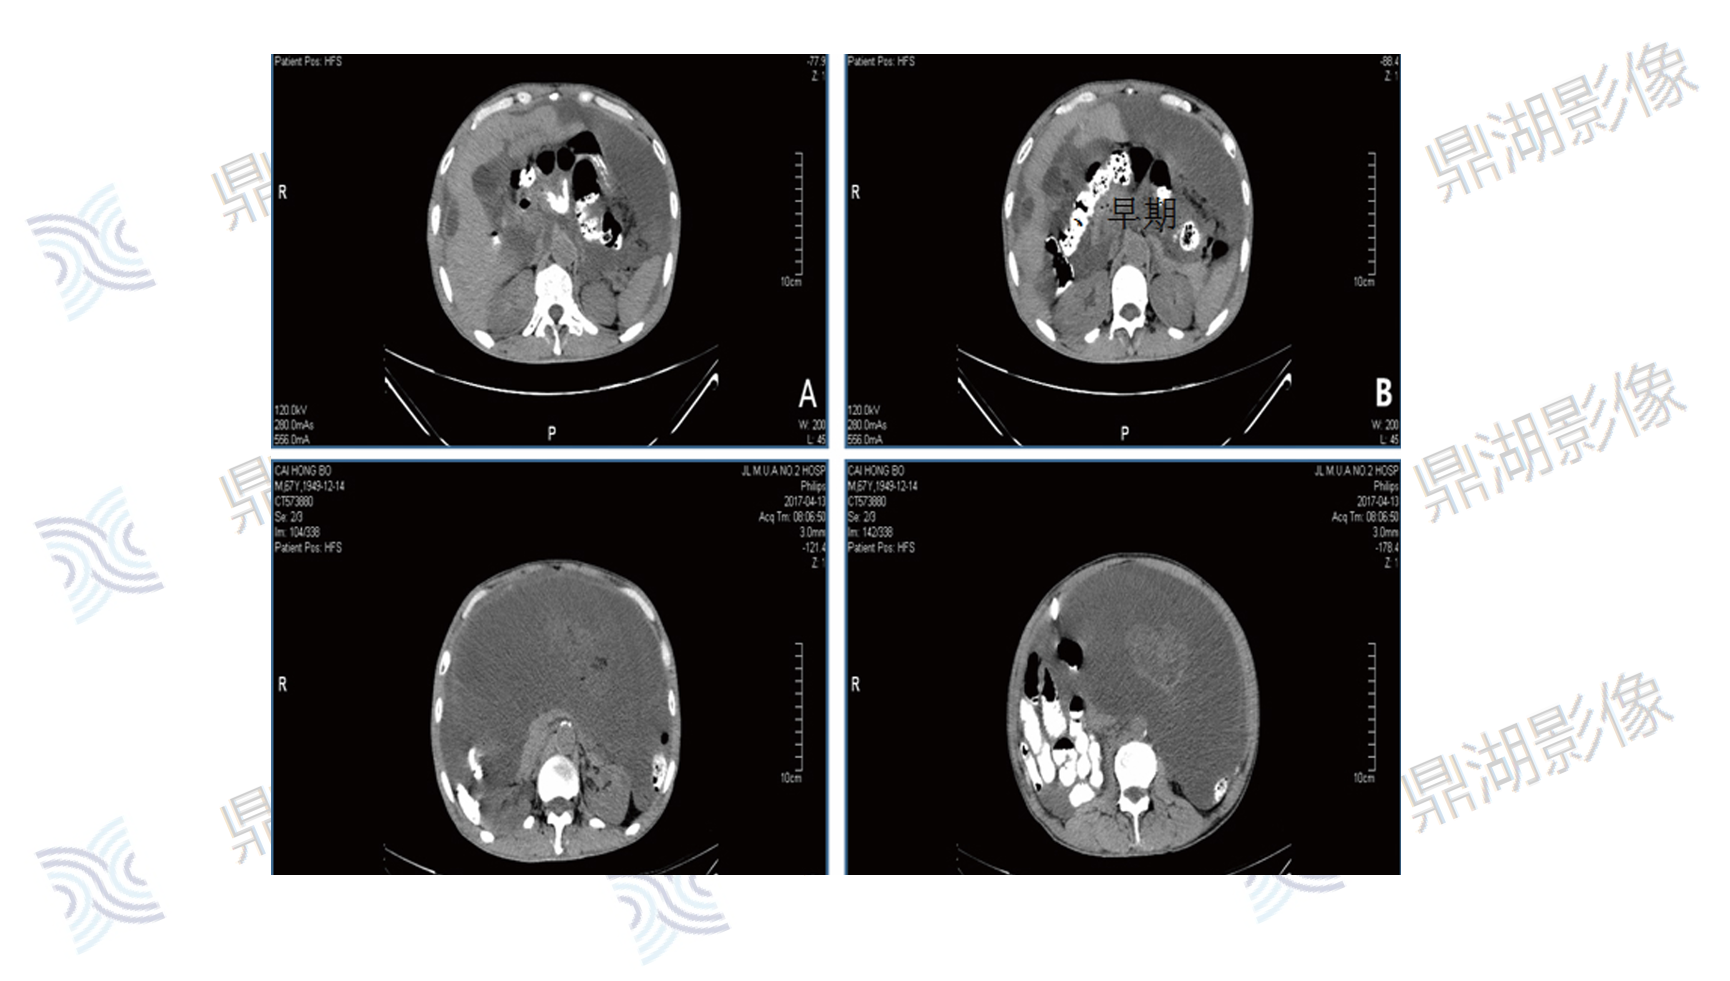

腹部上皮样间皮瘤

主诉:腹痛10天,CT检查示腹膜结节及肿块,腹腔积液;血红蛋白减低